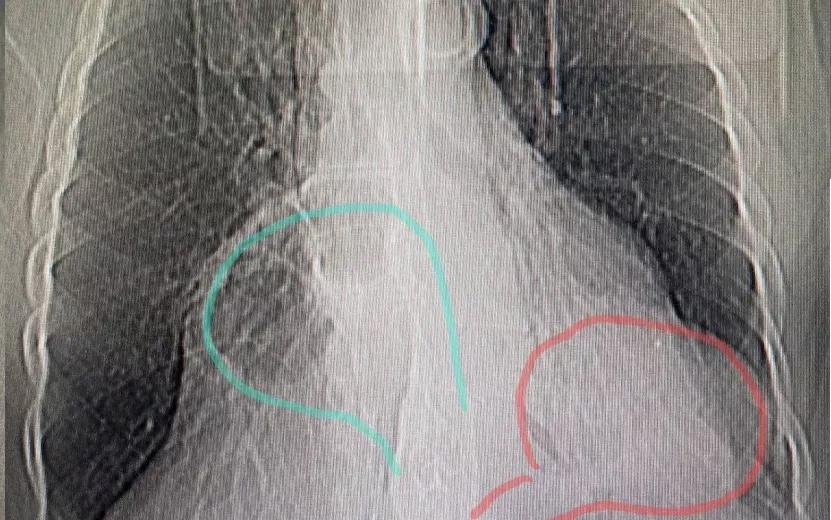

Врачи Городской клинической больницы № 9 Ижевска провели уникальную операцию. Доктора столкнулись с редкой патологией – сочетанием грыж кишечника и диафрагмы, сообщает на своей странице вице-премьер Удмуртии Эльвира Пинчук. В Центр торакальной хирургии обратилась 78-летняя жительница республики с жалобами на сильные боли в области грудной клетки. В ходе обследования у нее нашли две грыжи, которые разрослись до 15 см.